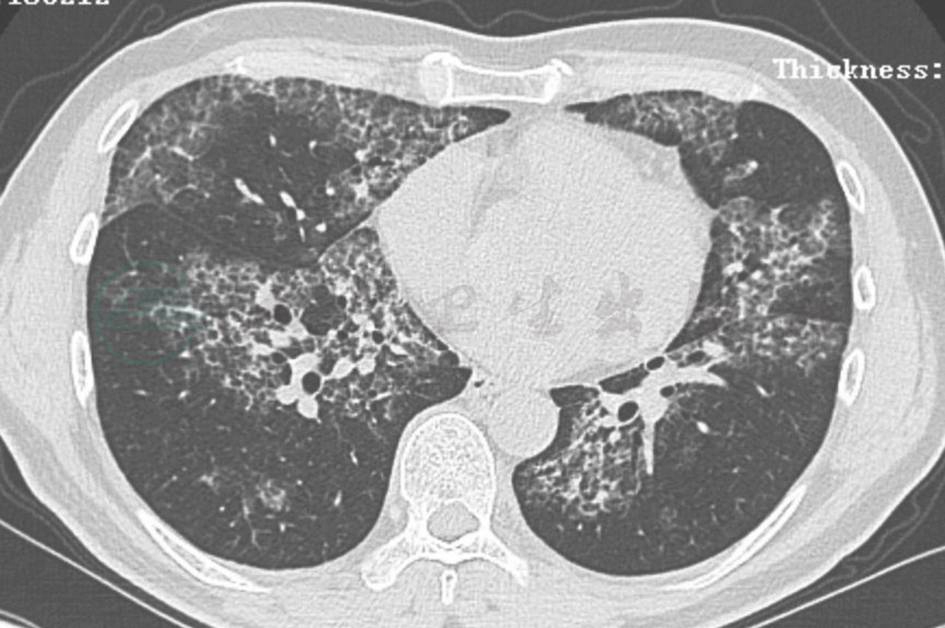

鉴于患者胸部影像学表现有明显进展(图1C),行电视辅助胸腔镜检查,分别钳取右肺上、下叶组织各一块,送病理检查。肺组织病理示细支气管黏膜下形成良好的上皮肉芽肿,朗格汉斯巨细胞包绕,中心有干酪样坏死(图7);组织抗酸染色阳性(图8)。病理确诊为肺结核。

图7 肺组织病理表现

胸腔镜术后病理提示沿细支气管黏膜下(黑色箭头)分布多灶肉芽肿性结构(白色箭头),可见多核巨细胞反应,以及中心性干酪样坏死(HE染色,100×)